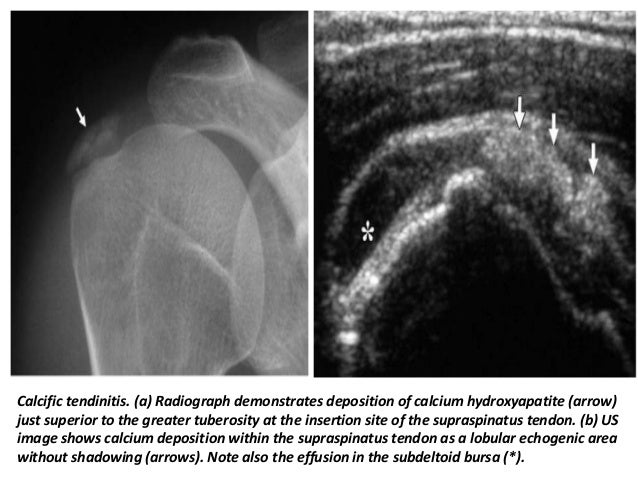

36. 36. Calcific tendinitis. (a) Radiograph demonstrates deposition of calcium hydroxyapatite (arrow) just superior to the greater tuberosity at the insertion site of the supraspinatus tendon. (b) US image shows calcium deposition within the supraspinatus tendon as a lobular echogenic area without shadowing (arrows). Note also the effusion in the subdeltoid bursa (*).